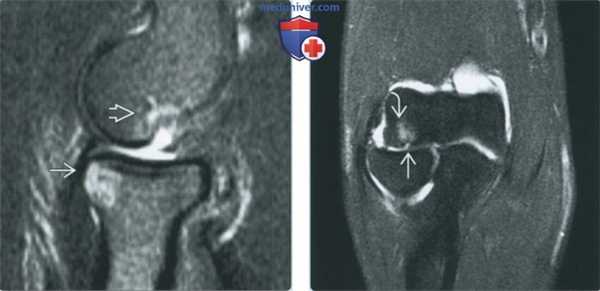

(Слева) МР-артрография в режиме PD FS, сагиттальный срез: визуализируются последствия коано-хрящевого повреждения - свободное тело в переднем отделе сустава, остеофит и синовит.

(Справа) МР-артрография в режиме Т1ВИ, коронарный срез: в головке мыщелка плечевой кости отмечается локальный глубокий дефект хряща. Прилежащий отдел хряща имеет неровный контур. Пациент молодого возраста занимался бейсболом.